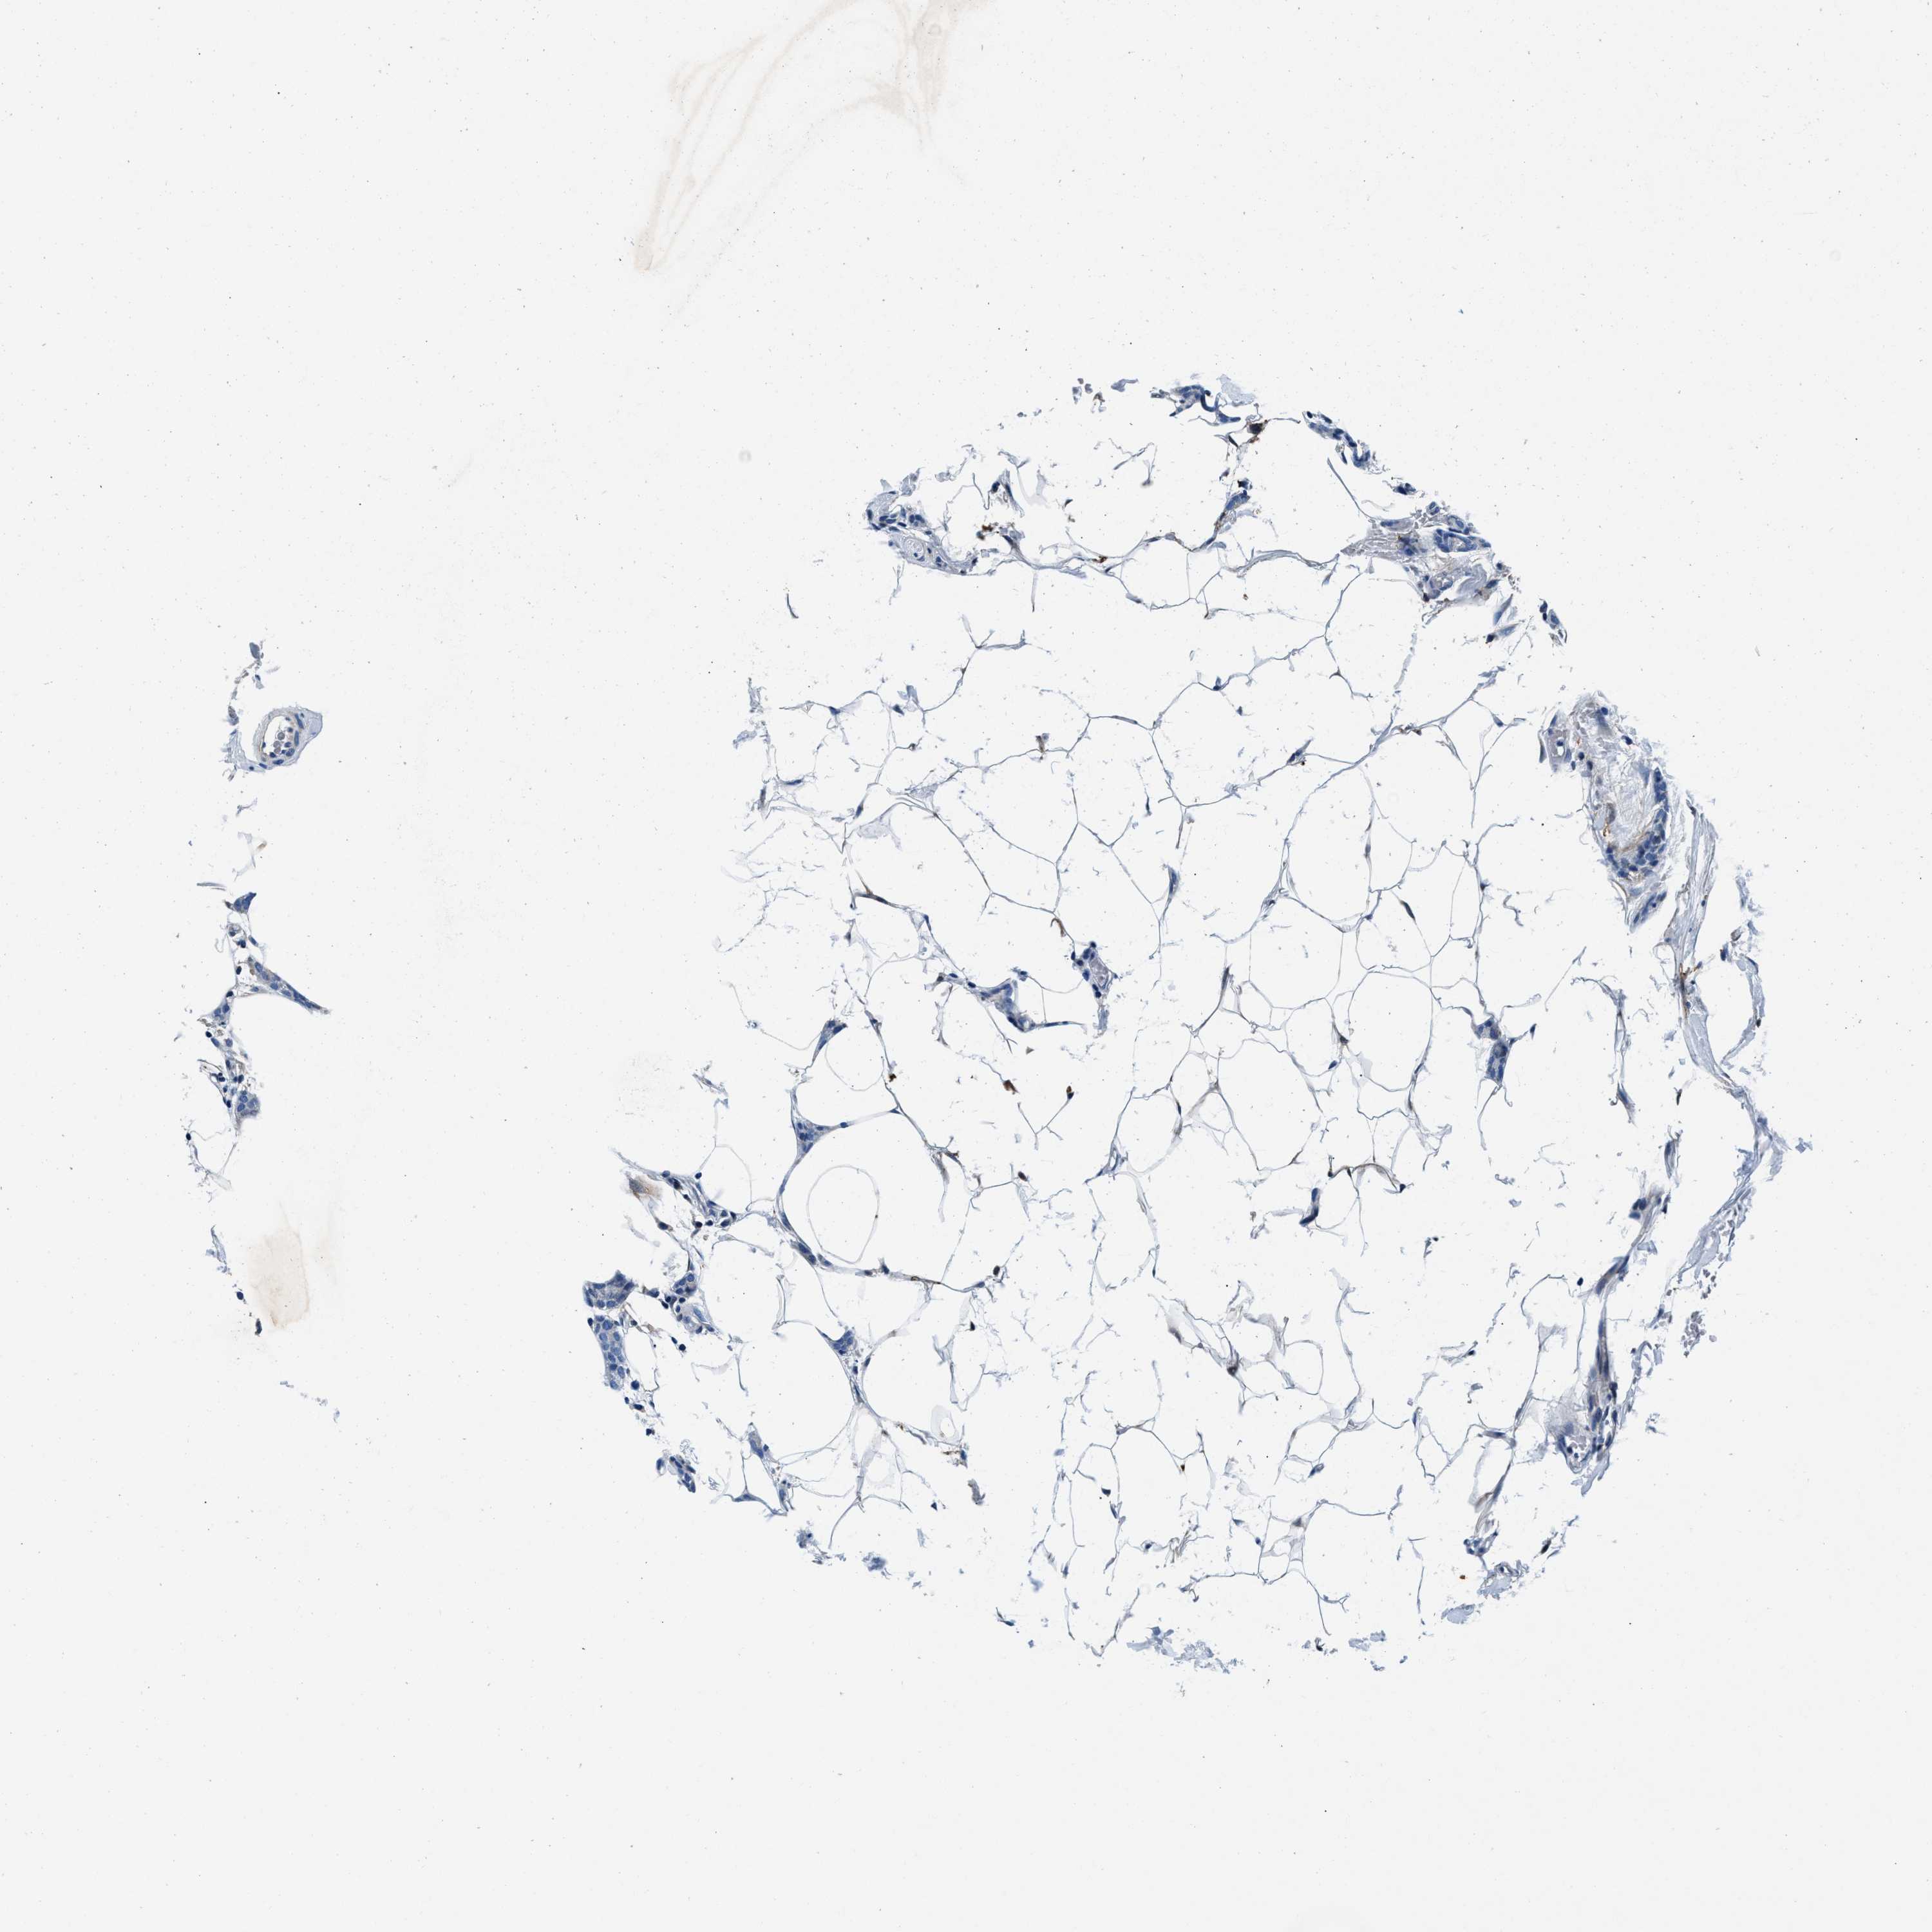

CANCER BREAST CANCER Show tissue menu

BRCA TCGA BRCA VALIDATION PROTEIN EXPRESSION